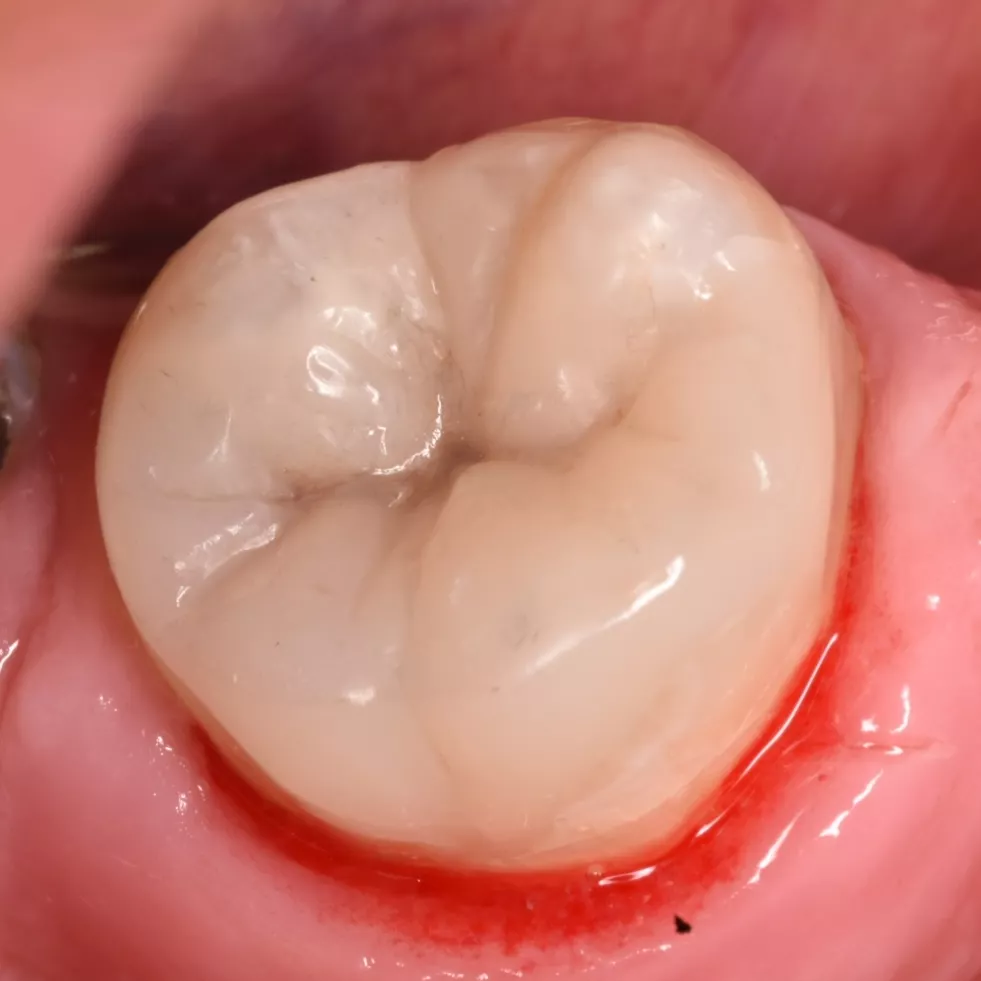

Final result after finishing and polishing

12 months follow-up